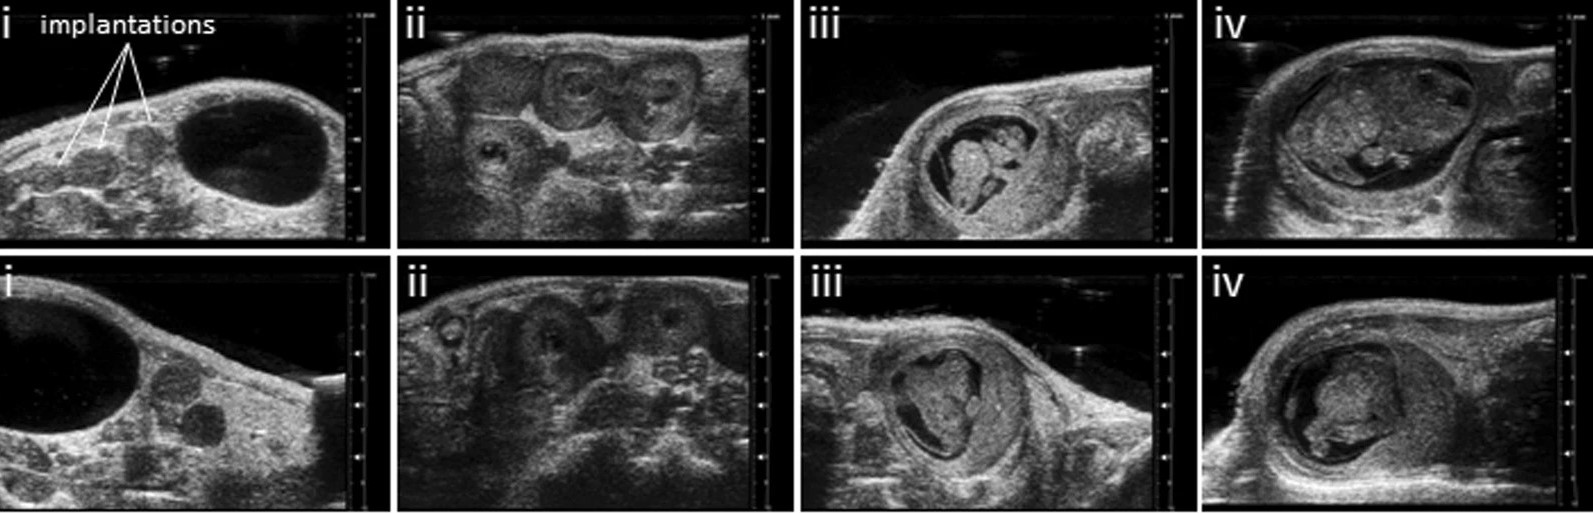

Absence of heme oxygenase-1 affects trophoblastic spheroid implantation and provokes dysregulation of stress and angiogenesis gene expression in the uterus